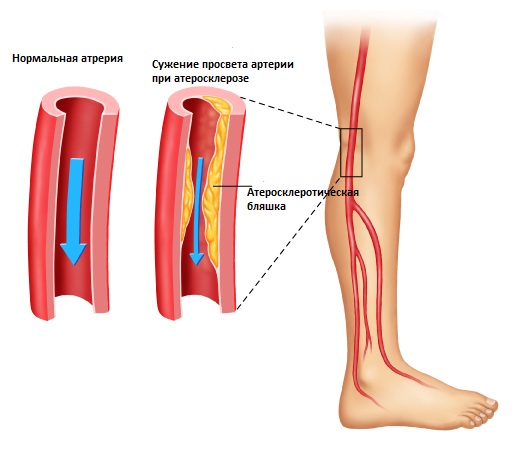

Стеноз периферических артерий нижних конечностей

Стеноз сосудов ног представляет собой заболевание, при котором происходит сужение или полное закрытие артерий нижних конечностей, что нарушает нормальный кровоток в ногах. Главной причиной сужения периферических артерий является атеросклероз. Атероматозные бляшки, образующиеся на стенках сосудов, препятствуют кровоснабжению, что приводит к недостатку кислорода в мышцах и тканях ног.